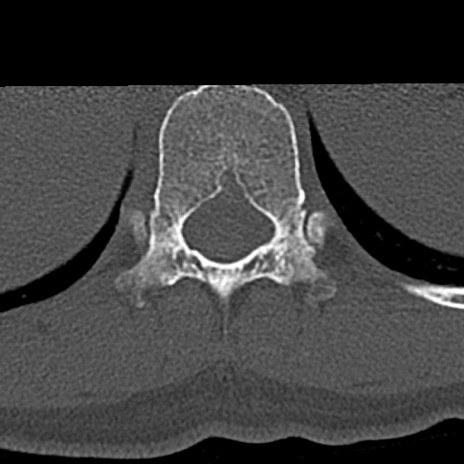

腰椎CT

横断像と矢状断像